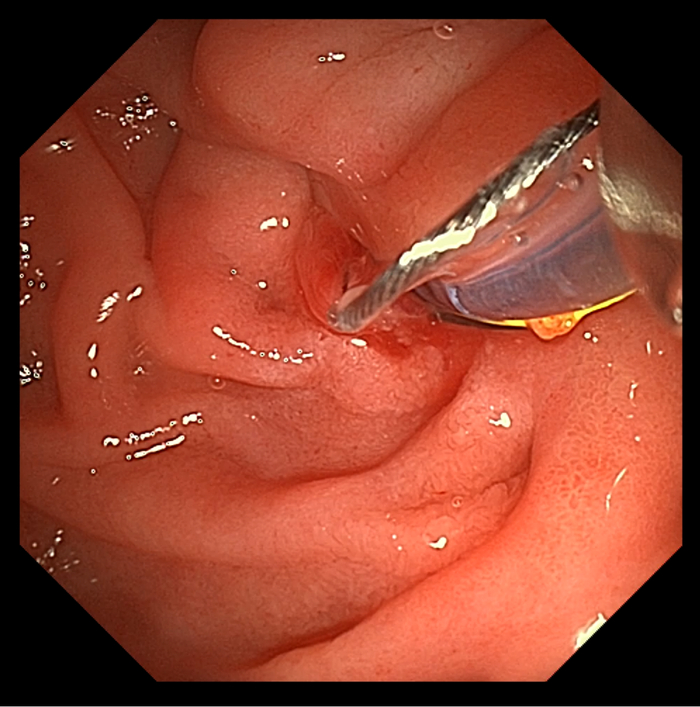

患者男,56岁,十二指肠镜提示慢性胰腺炎,CT下显示胰管结石。

CT下可见,结石狭窄处

导丝已插入胰管(右上

由此病例可见,即使是面对高难度的双导丝技术胰管内取石,澳华全新UHD系列十二指肠镜仍然可以凭借良好的操控性能,让医者诊疗时十分得心应手。且在更大的抬钳器角度的匠心设计下,医生可以更轻松、准确地插入耗材,大幅缩短手术时间。